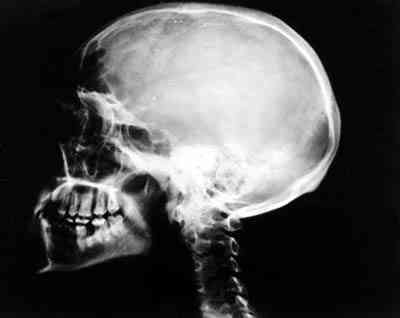

Figura 2

RADIOGRAFÍA SIMPLE DE CRÁNEO EN PROYECCIÓN LATERAL HACE 8 AÑOS, PREVIA A CIRUGÍA.